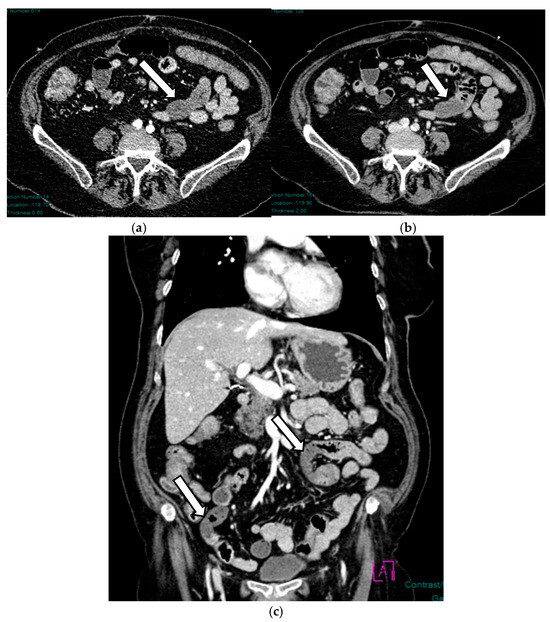

Acute mesenteric ischemia (AMI) is a clinical condition caused by vascular insufficiency, resulting in intestinal damage. Is often underestimated, if not driven by clinical suspicion, due to the non-specific clinical symptoms (usually represented by acute abdominal pain) and the absence of reliable markers, which results in a poor prognosis and high mortality. We can identify three main forms of AMI: arterial, venous, and non-occlusive. Arterial AMI is the most frequent form, caused by occlusion of the superior mesenteric artery or one of its branches. Venous AMI is the least frequent, caused by thrombosis of the superior mesenteric vein or its branches. Non-occlusive AMI is due to a state of hypovolemia, which is frequent in patients who have undergone surgery. Given the difficulty of diagnosis based on the clinic alone, the radiologist plays a central role in identifying radiological signs of intestinal ischemia and in avoiding misdiagnosis. The radiologist’s role is mainly to identify factors predictive of necrosis, which allow us to stratify patients and direct them towards the proper management. The aim of this review is to provide indications for an adequate CT protocol, including an unenhanced phase, an arterial phase, and a venous phase, as well as to underline the features to investigate in the different forms of AMI, in order to increase the diagnostic capacity in this challenging disease. Full article

Show Figures

Figure 1